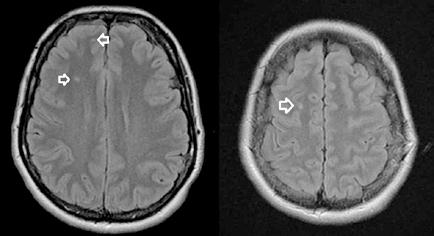

Ante la persistencia de la bradipsiquia y la dificultad para ejecutar órde nes moderadamente complejas, a pesar de que la madre decía que no veía grandes diferencias con respecto a su estado basal, se solicitó una resonan cia magnética cerebral. En la resonancia magnética se observó una altera ción de la intensidad de la señal en la porción central del cuerpo calloso, en concreto en esplenio y rodilla, con hiperintensidad en T2, hipointensidad en T1 basal y moderada restricción de la difusión; hallazgos que eran com patibles con el Síndrome Marchiafava-Bignami (Figura 3).

Se citó nuevamente en la consulta de Medicina Interna, apreciándose cierta mejoría subjetiva a nivel cognitivo, ganancia ponderal (64 kg) y difi cultades para la marcha. En la RMN solicitada meses después no se observó mejoría alguna, sino una progresión de la enfermedad con aparición de necrosis, atrofia y aumento de difusión en el esplenio del cuerpo calloso (Figura 4).

Figura 3.

Resonancia magnética. Secuencia T1 y T2. Cortes sagital y transversal. Estudio artefactado por el movimiento del paciente. Estudio T1 donde se aprecia una lesión hipointensa con moderada restricción a la difusión en las capas medias del esplenio del cuerpo calloso, que en la secuencia T2 corresponde con una lesión hipertensa. Esta lesión en dicha localización y en el contexto clínico del paciente es altamente sugestiva de Marchiafava-Bignami.

Figura 4. Resonancia magnética cerebral a los 8 meses. Secuencias T1, T2 y difusión, corte sangital y transversal. En el esplenio del cuerpo calloso se observa adelgazamiento, con presencia de un área de necrosis en las capas medias de hiperintesidad de señal periférica con aumento de difusividad. En comparación con RM previe se objetivan cambios evolutivos con necrosis, atrofia y aumento de la difusión. Hallazgos compatibles con la enfermedad de Maarchiafava-Bignami.